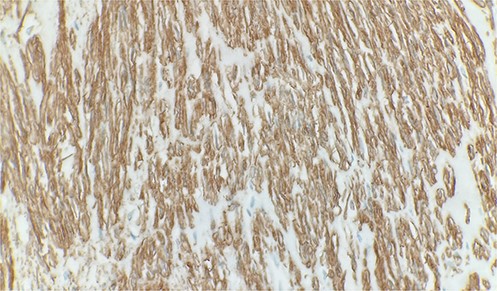

A 70-year-old male patient with a history of prostatic adenocarcinoma presented with testicular swelling. Testicular ultrasound revealed a 4 cm hypoechoic mass at the level of the epididymis. The patient underwent a radical orchiectomy. Pathology demonstrated a 4 cm mass located around the epididymis that was composed of elongated spindle cells arranged in intersecting fascicles. The tumor cells were found to have cigar-shaped nuclei and fibrillary eosinophilic cytoplasm (Fig. 1). Most of the lesions indicated relatively monomorphic cytology. Scattered moderate-to-focally marked nuclear pleomorphism was present. Focal necrosis was present, which may be suggestive of more aggressive biologic behavior. Ki 67% was approximately 10% and the mitotic activity was 7 mitotic figures per 10 high power-fields. The tumor margins were negative, with no invasion of the testicular parenchyma or spermatic cord. Immunohistochemistry showed strong reactivity with desmin and smooth muscle actin (Fig. 2). Overall, findings were diagnostic of low-grade leiomyosarcoma.

Microscopic examination reveals intersecting fascicles of monotonous spindle cells with indistinct borders, eosinophilic cytoplasm and cigar-shaped nuclei. There is necrosis on the right upper portion. Hematoxylin and Eosin 20×.